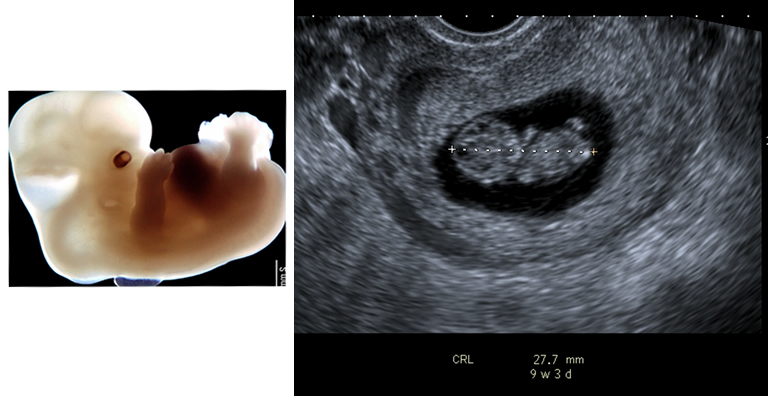

By 9 weeks, the baby is beginning to take shape. This one now measures nearly 28 mm long. You can clearly see it has a head and body and that the limbs are beginning to form.

| Fig 1 Reproduced with kind permission from Brad Smith, University of Michigan; NICHHD: NO1 HD 6 3257 |